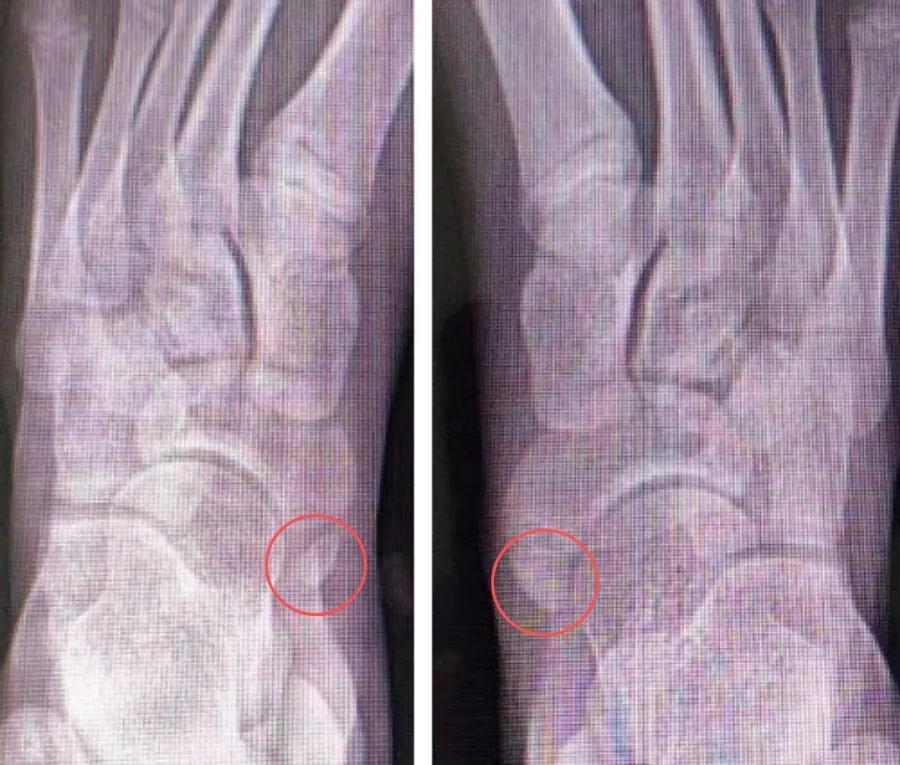

外观照及查体:典型体征可见足内侧突起、压痛(下图)。

X线:足舟骨结节内后方有边缘整齐的小骨块,密度同舟骨(下图)。